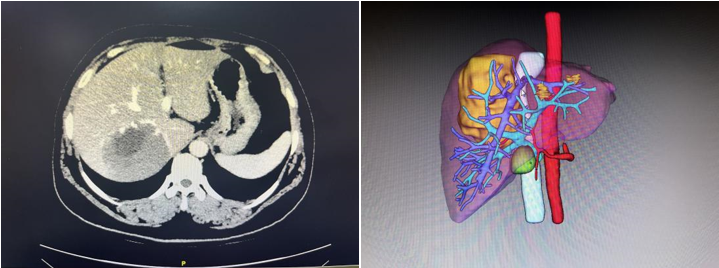

52岁的王女士一周前因腹痛并发双下肢水肿于当地医院检查发现肝脏上有一类椭圆形巨大肿瘤。在当地医生推荐下,来到ac米兰官网中文网站一院肝脏外科就诊。入院后,陆朝阳教授团队,通过科学精密的术前检查和3D成像技术,明确肿瘤位于肝脏右后叶和尾状叶,如成年男性拳头大小,确诊为肝血管瘤,肿瘤体积巨大且位于肝脏S7段及尾状叶腔旁部并紧邻人体几条重要大血管(下腔静脉、右肝静脉、右侧门静脉),其中肿瘤后壁全程压迫整个肝后下腔静脉,右肝静脉被肿瘤头侧压扁血流流出受阻,肿瘤左侧位于肝脏尾状叶(腔旁部)曾一度被称为手术禁区,手术难度已是极大。但不仅如此,患者肝脏血管畸形,右后下肝静脉(多长一条右肝静脉)位于肿瘤足侧,将传统肝右后叶微创手术路径彻底封死,这导致想要将肿瘤安全地微创切除甚至开刀切除几乎不可能完成。

▲图1术前肝脏CT、三维可视化提示肿瘤所在位置